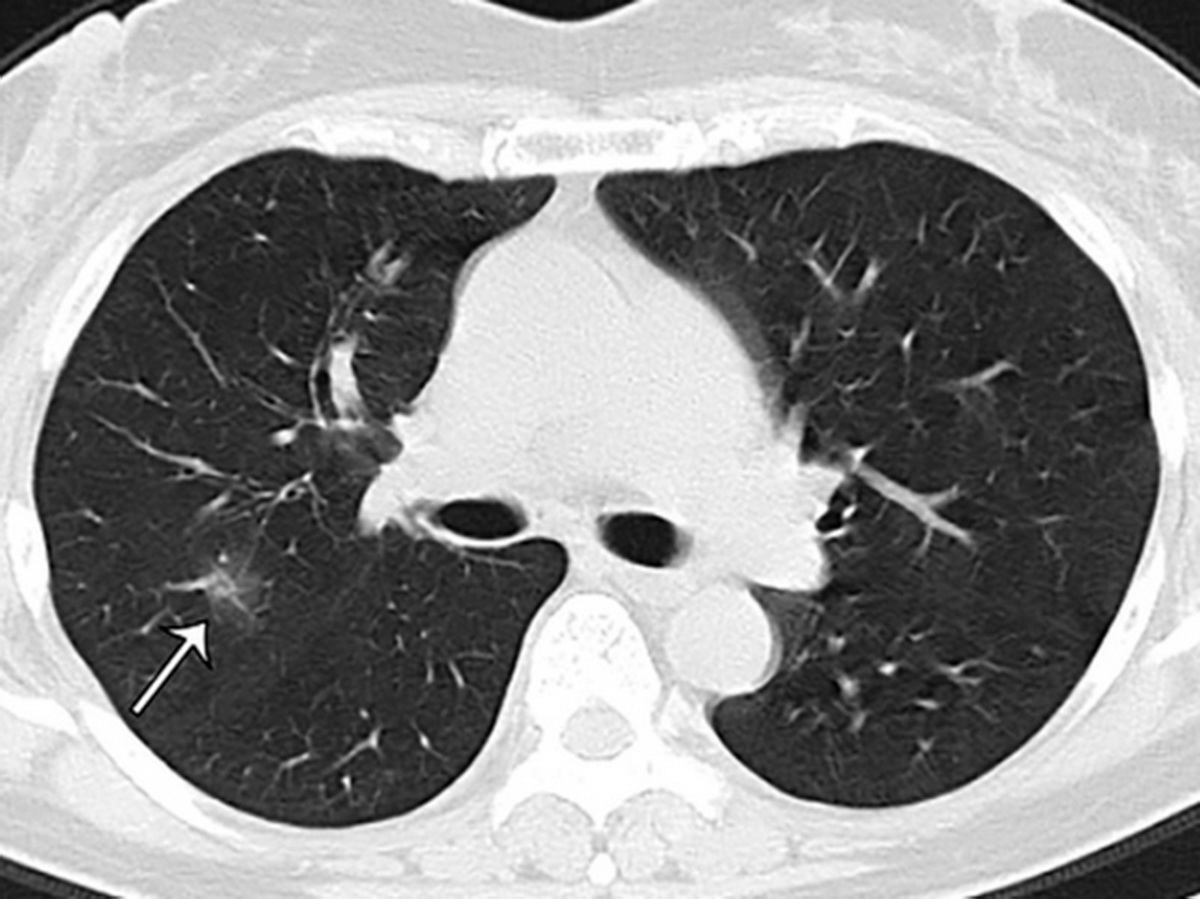

Матовое стекло коронавирус кт

Пневмония кт матовое стекло

Матовое стекло на кт

Фото рентгеновских снимков поражения легких при COVID-19

На фотографиях рентгеновских снимков видно, как вирус воздействует на легочную ткань. Характерные признаки поражения легких включают пятна, инфильтраты и наличие жидкости внутри легочных альвеол.

Фото рентгеновских снимков помогают врачам и специалистам визуально определить степень поражения легких и принять соответствующие меры лечения и поддержки пациента.